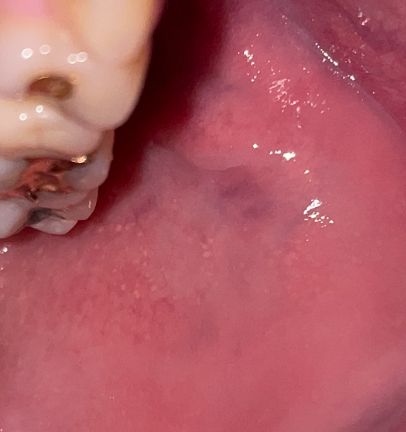

구강 볼 안쪽 점막에 하얀 돌기들과 통증은 어떤 질병인가요?

따끔 거리고 화끈거리는 통증이 있는데 이게 편평태선이라는 질병인지 홍반증인지 궁금합니다 없어지지 않고 있는데 냅둬도 되는 건가요 구강암으호 변하는 질병은 아니겠죠? 왼쪽 볼에만 있습니다 혹시나 잘때 이갈이 장치를 착용하는디 그거때문에 생긴 건가요?

• 1번 째 사진

하얀 돌기와 통증이 있는 증상은 여러 가지 원인에 의해 발생할 수 있습니다만, 장치를 새로 착용하게 된 경우, 구강 점막에 자극이 가해져 증상이 발생했을 가능성이 있습니다.